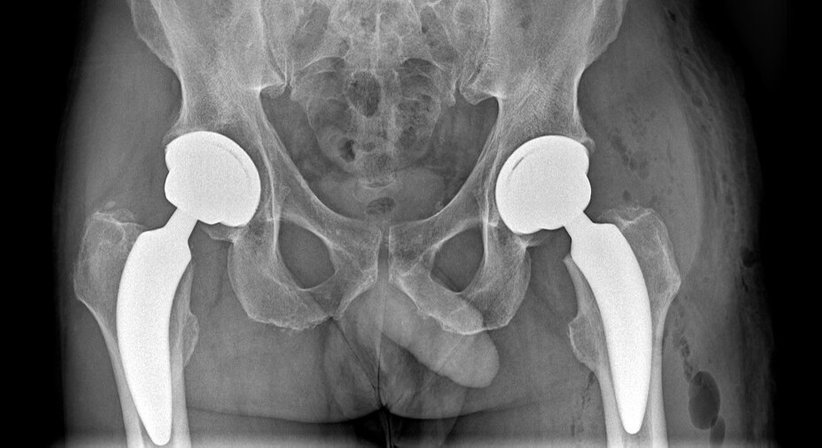

Minimal-invasive Hüftendoprothetik/Minimal-invasiver Hüftgelenksersatz

Die Anwendung von sogenannten „Kurzschaftprothesen“ ermöglicht zusätzlich eine noch schonendere und gewebefreundlichere Operationstechnik. Welches Implantat gewählt wird, entscheidet jedoch die Anatomie und der Zustand des Knochens - Faktoren wie Osteoporose, Weite des Markraumes etc. spielen eine wesentliche Rolle, daher ist eine präoperative Planung mittels spezieller Computer Software (Vermessungsprogramm) obligat.